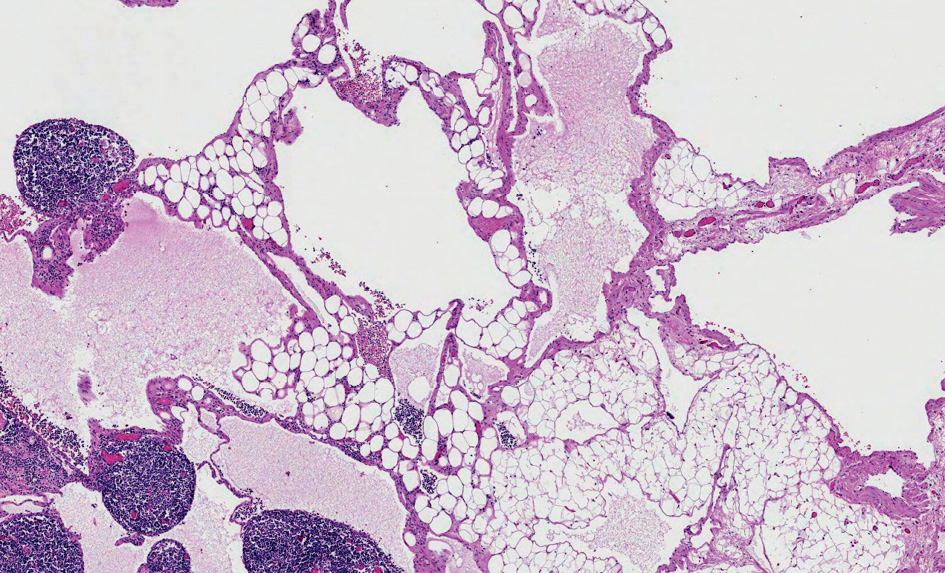

On pathological examination, the macroscopically observed partially opened fatty-fibrous cystic formation 9 cm × 5 cm × 3 cm was identified. Cysts of up to 2 cm filled with whitish, turbid substance were visible. 6 lymph nodes up to 0.5 cm were excised alongside with the lymphangioma. Histologically thin-walled cystic tumor structures were separated by areas of adipose tissue with lymphoid aggregates (Fig. 6). The cavities of the mass were filled with eosinophilic fluid and lymphocytes. The fluid color is similar to milk due to the accumulation of lymphocytes (Fig. 5). Lymphoid aggregates and lymph nodes with histiocytosis were found in the surrounding tissue. Immunohistochemical examination of the lymphatic endothelial marker podoplanin (D2-40) was positive in the endothelial wall of the cystic tumor (Fig. 7). Histological findings support the diagnosis of lymphangioma.